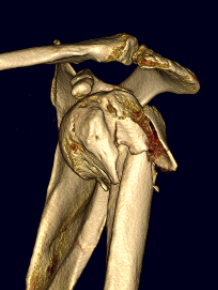

Four part